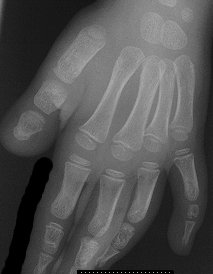

Apert Syndrome

• coronal, sagittal, lambdoidal

• symmetrical syndactyly of hands/feet